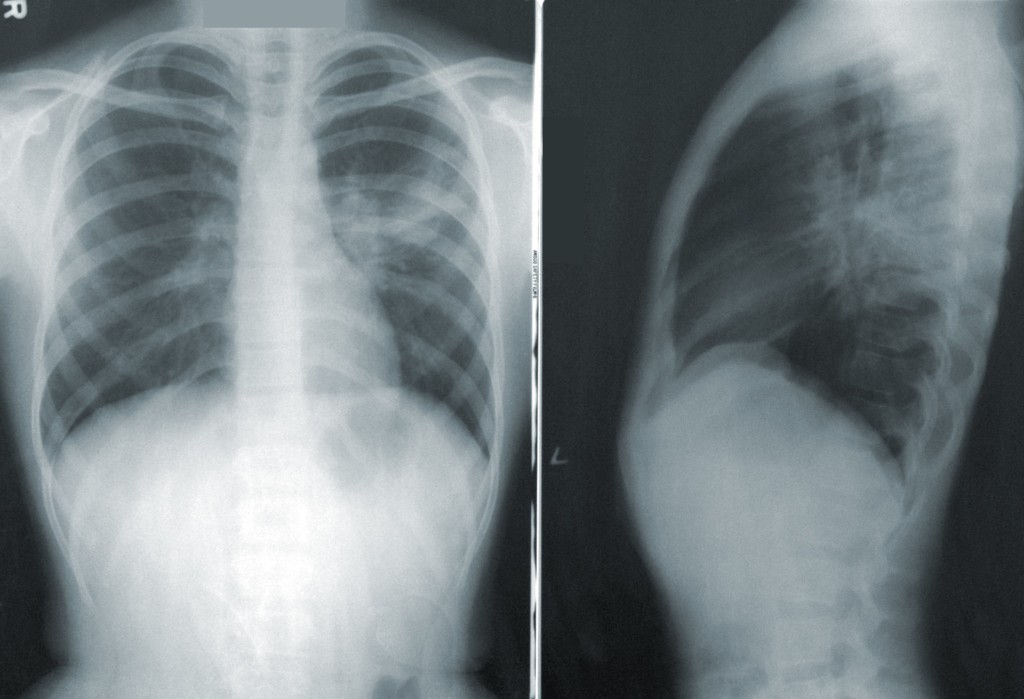

Computerized Tomography (CT) scans have also been used to diagnosis the disease, and there was promising research around using machine learning to interpret results quickly. Unfortunately, not every hospital or clinic has access to CT equipment. The PVAMU CREDIT team decided to investigate whether X-rays, which are widely available and relatively inexpensive for health care providers, could yield similar results.

“We started with a public dataset of 13,800 chest x-ray images,” said Qian. “The x-rays were divided into three groups: normal, pneumonia (not COVID-19 related), and COVID-19. From there, we used two deep learning models to create experiments to see if machine learning could accurately identify the COVID-19 images.”

The team eventually found a “sweet spot,” where a certain model was able to recognize the COVID-19 images with good performance. In summary, their research could cut down on the need for other types of testing that take longer, thus improving the speed of quarantine and treatment.

This is the first stage of research, and more testing will be done as new public datasets become available in the coming months. As the project progresses, the team hopes to provide a highly accurate and efficient way for health care professionals to detect COVID-19 using a simple chest x-ray.